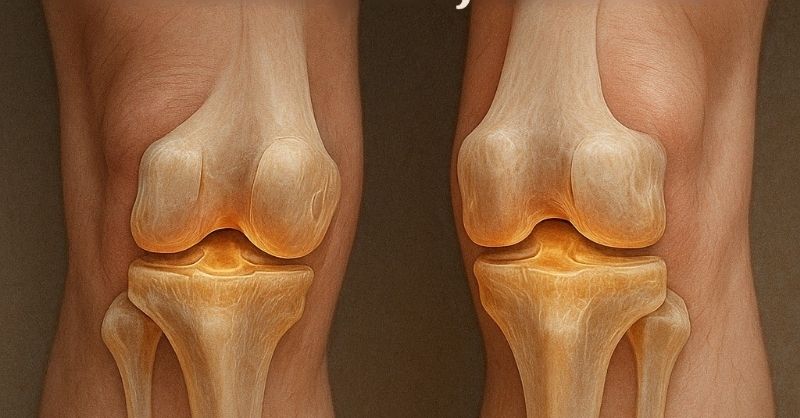

15 Years of Pain Gone in Minutes! Discover the Secret to Joint Relief!

Joint pain can become a real struggle, especially when it interferes with daily life. If you’ve been searching for natural relief, you might want to explore essential oils...

Vegetables that Strengthen Collagen in Knees and Joints

Collagen is one of the most important proteins in the human body. It serves as a core building block for connective tissues, including cartilage, tendons, skin, and bones....